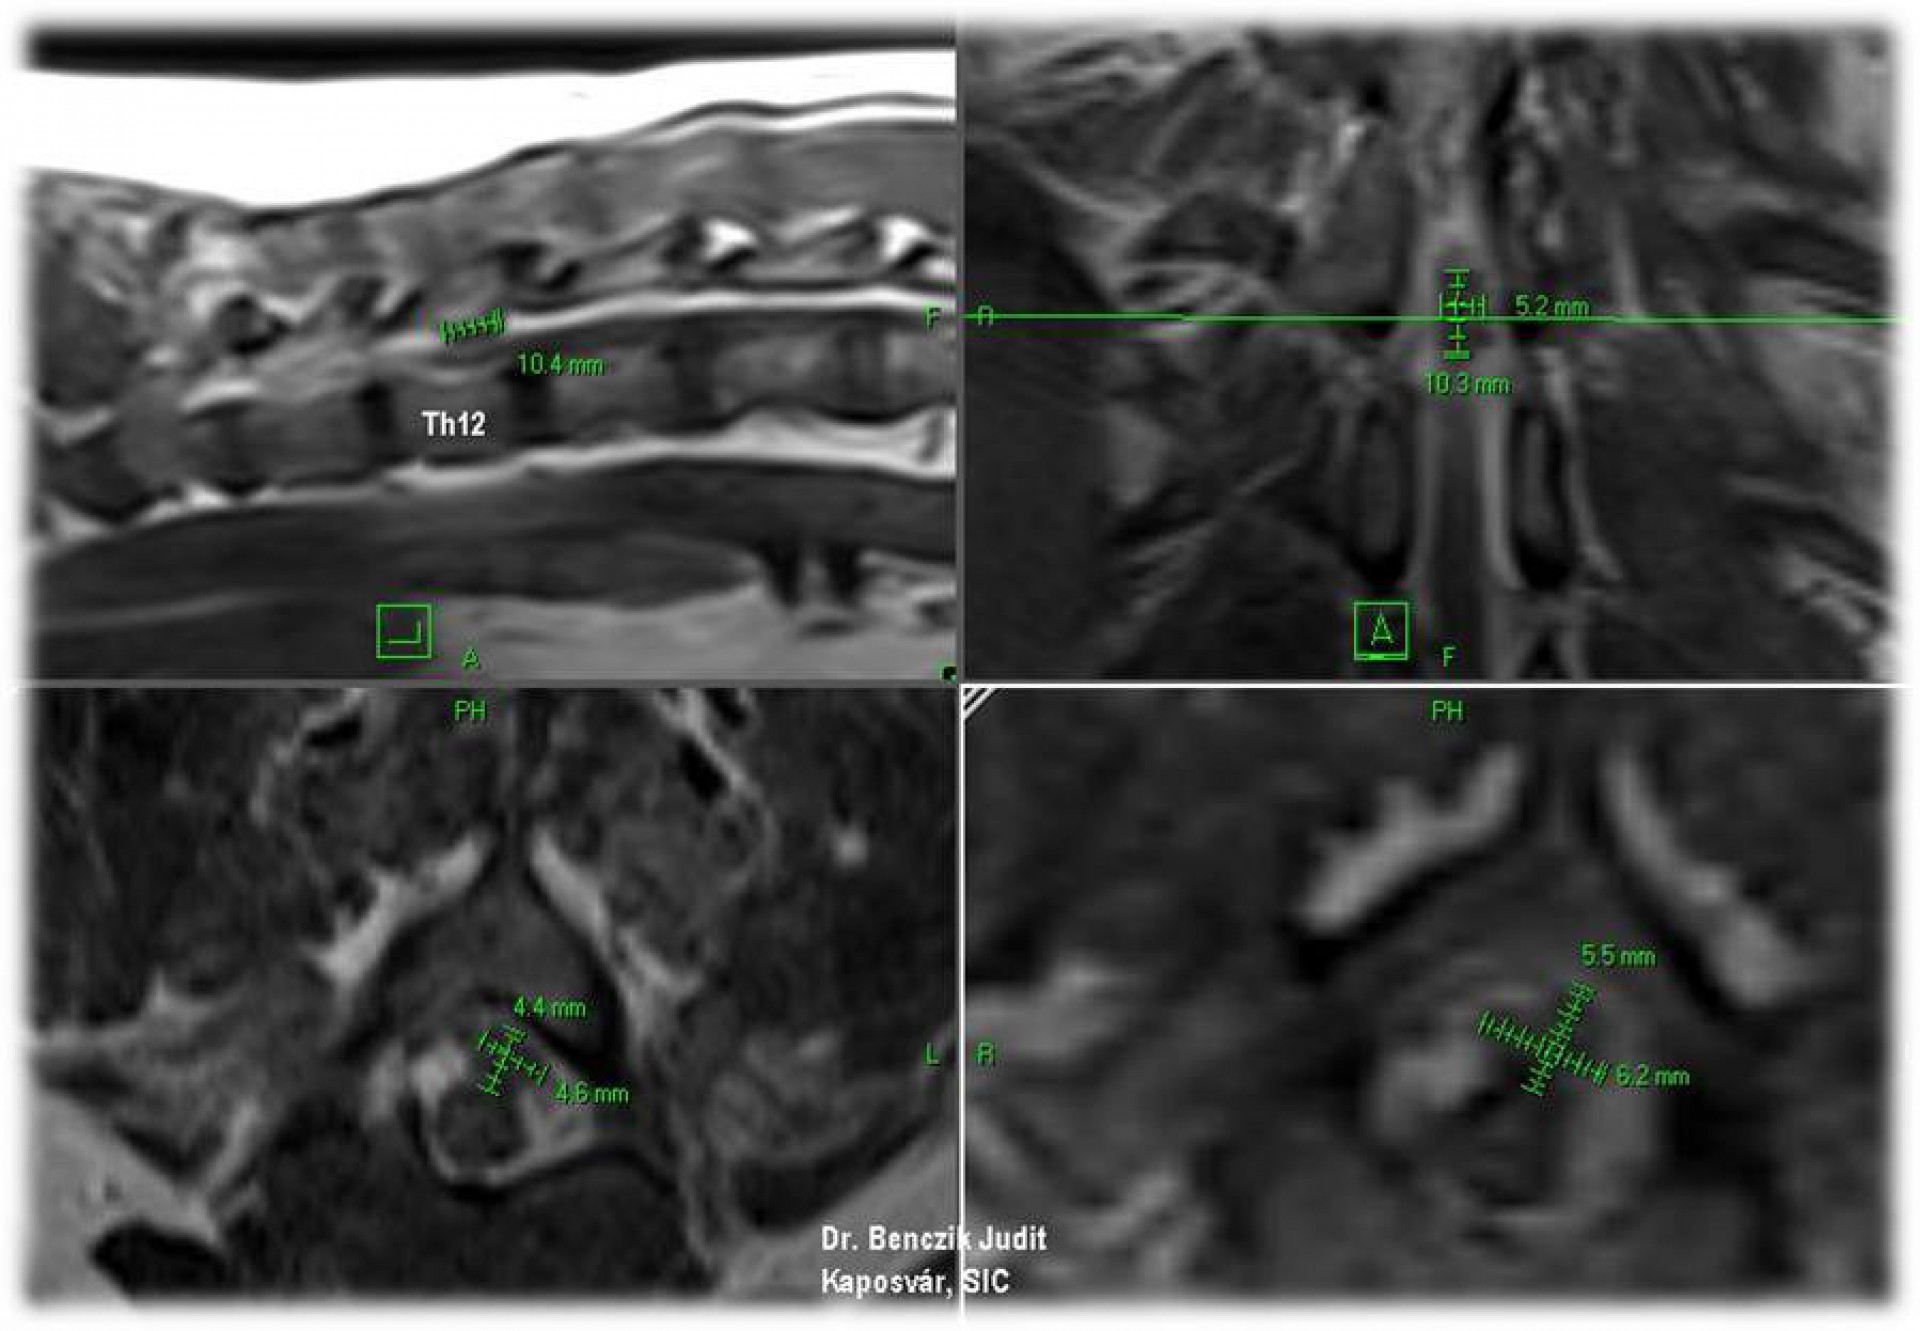

Míg az utóbbi esetben az elsődleges daganat eltávolítását, szövettani vizsgálatát követően az áttétes daganatok kemoterápiás/ sugárterápiás gyógykezelési lehetősége merül fel elsődlegesen, addig a primer gerincdaganatok kialakulása esetén annak pontos lokalizációját, a gerincoszlop alkotóelemeinek érintettségének maghatározását követően a daganat műtéti eltávolítására is sor kerülhet.A klinikai tünetek kialakulása sokféle lehet, szinte minden esetben egy folyamatosan rosszabbodó, idegrendszeri tünetek súlyosbodásával járó, gyakran azonos oldali mellső és hátsó végtagot érintő neurológiai kiesést tapasztalunk. A klinikai tünetek alapján azonban a gerinc daganatos megbetegedései nem különíthetőek el a hasonló kórlefolyású degeneratív megbetegedésektől (pl.: porckorongsérv). Így a diagnózis pontos felállításához kiegészítő vizsgálatokra mindenképpen szükség van. Ezek közé tartozik a natív röntgenvizsgálat, de mivel a gerincvelő környéki, a csontvázat nem érintő daganatok többnyire nem adnak röntgenárnyékot, ezért az egyszerű röntgen vizsgálaton túl egyéb képalkotó eljárásokra, kiegészítő vizsgálatokra is szükség lehet.

A diagnózis felállítását követően az elsődleges gerincdaganatok esetén azok műtéti feltárása, lehetséges eltávolítása a gyógykezelés első és egyben legfontosabb lépése. A gerincvelő összenyomatásának megszüntetése a neurológiai funkció helyreállásának az alapfeltétele, de mivel a gerincvelő rendkívül rossz regenerációs képességekkel rendelkezik, így a már kialakult tünetek javulására nem minden esetben számíthatunk.! A műtétet követően az eltávolított kóros szövetszaporulatot a pathológiában jártas kollégáink szövettani vizsgálattal tovább vizsgálják, meghatározzák pontos eredetét és jó- vagy rosszindulatú voltát. A szövettani diagnózist követően a daganatterápia további részét képezheti a beteg állat kemoterápiás vagy sugárterápiás kezelése, mellyel az esetleg a műtéti területen maradt daganatsejtek további szaporodása, távoli áttétek kialakulása megelőzhető.